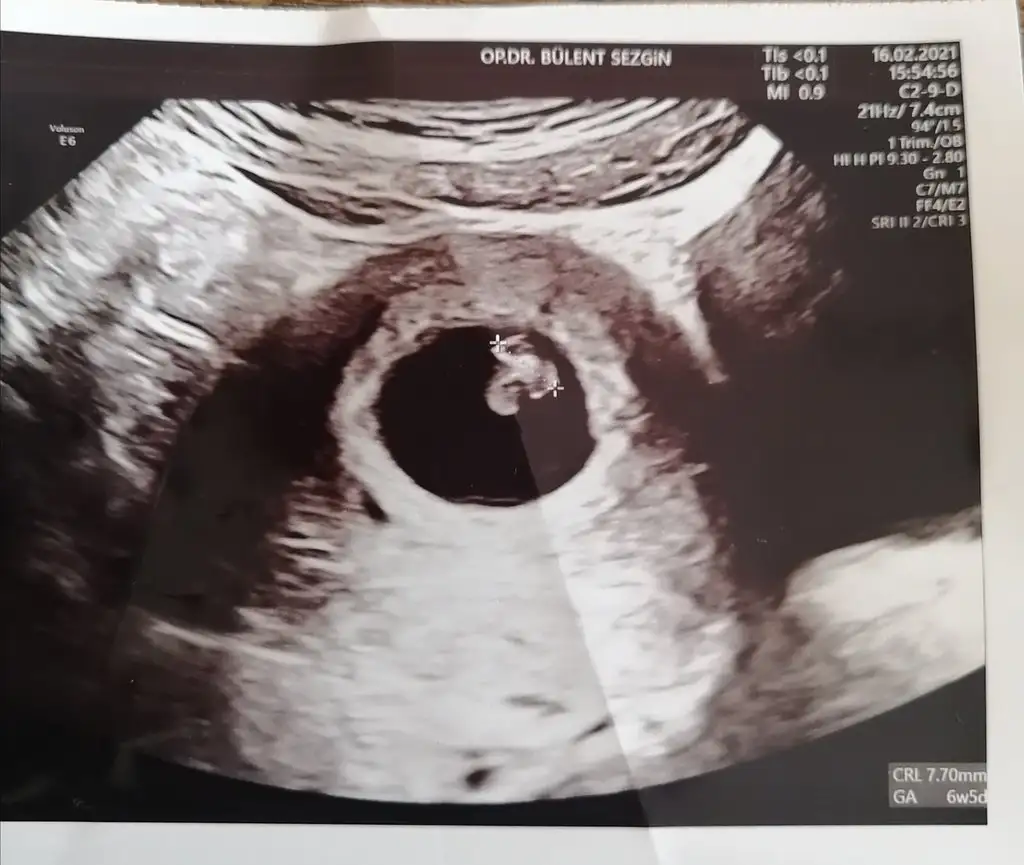

Selam kızlar bugün kalp atışına gittim 6+5 günlükmüşüz doktor doğumun 25 Eylül olacağını söyledi 😊 bu arada tüp bebek benim ki 🙏🏻🥰

Eklentiler

• IMG_20210216_173232.webp

IMG_20210216_173232.webp

34,2 KB · Görüntüleme: 63